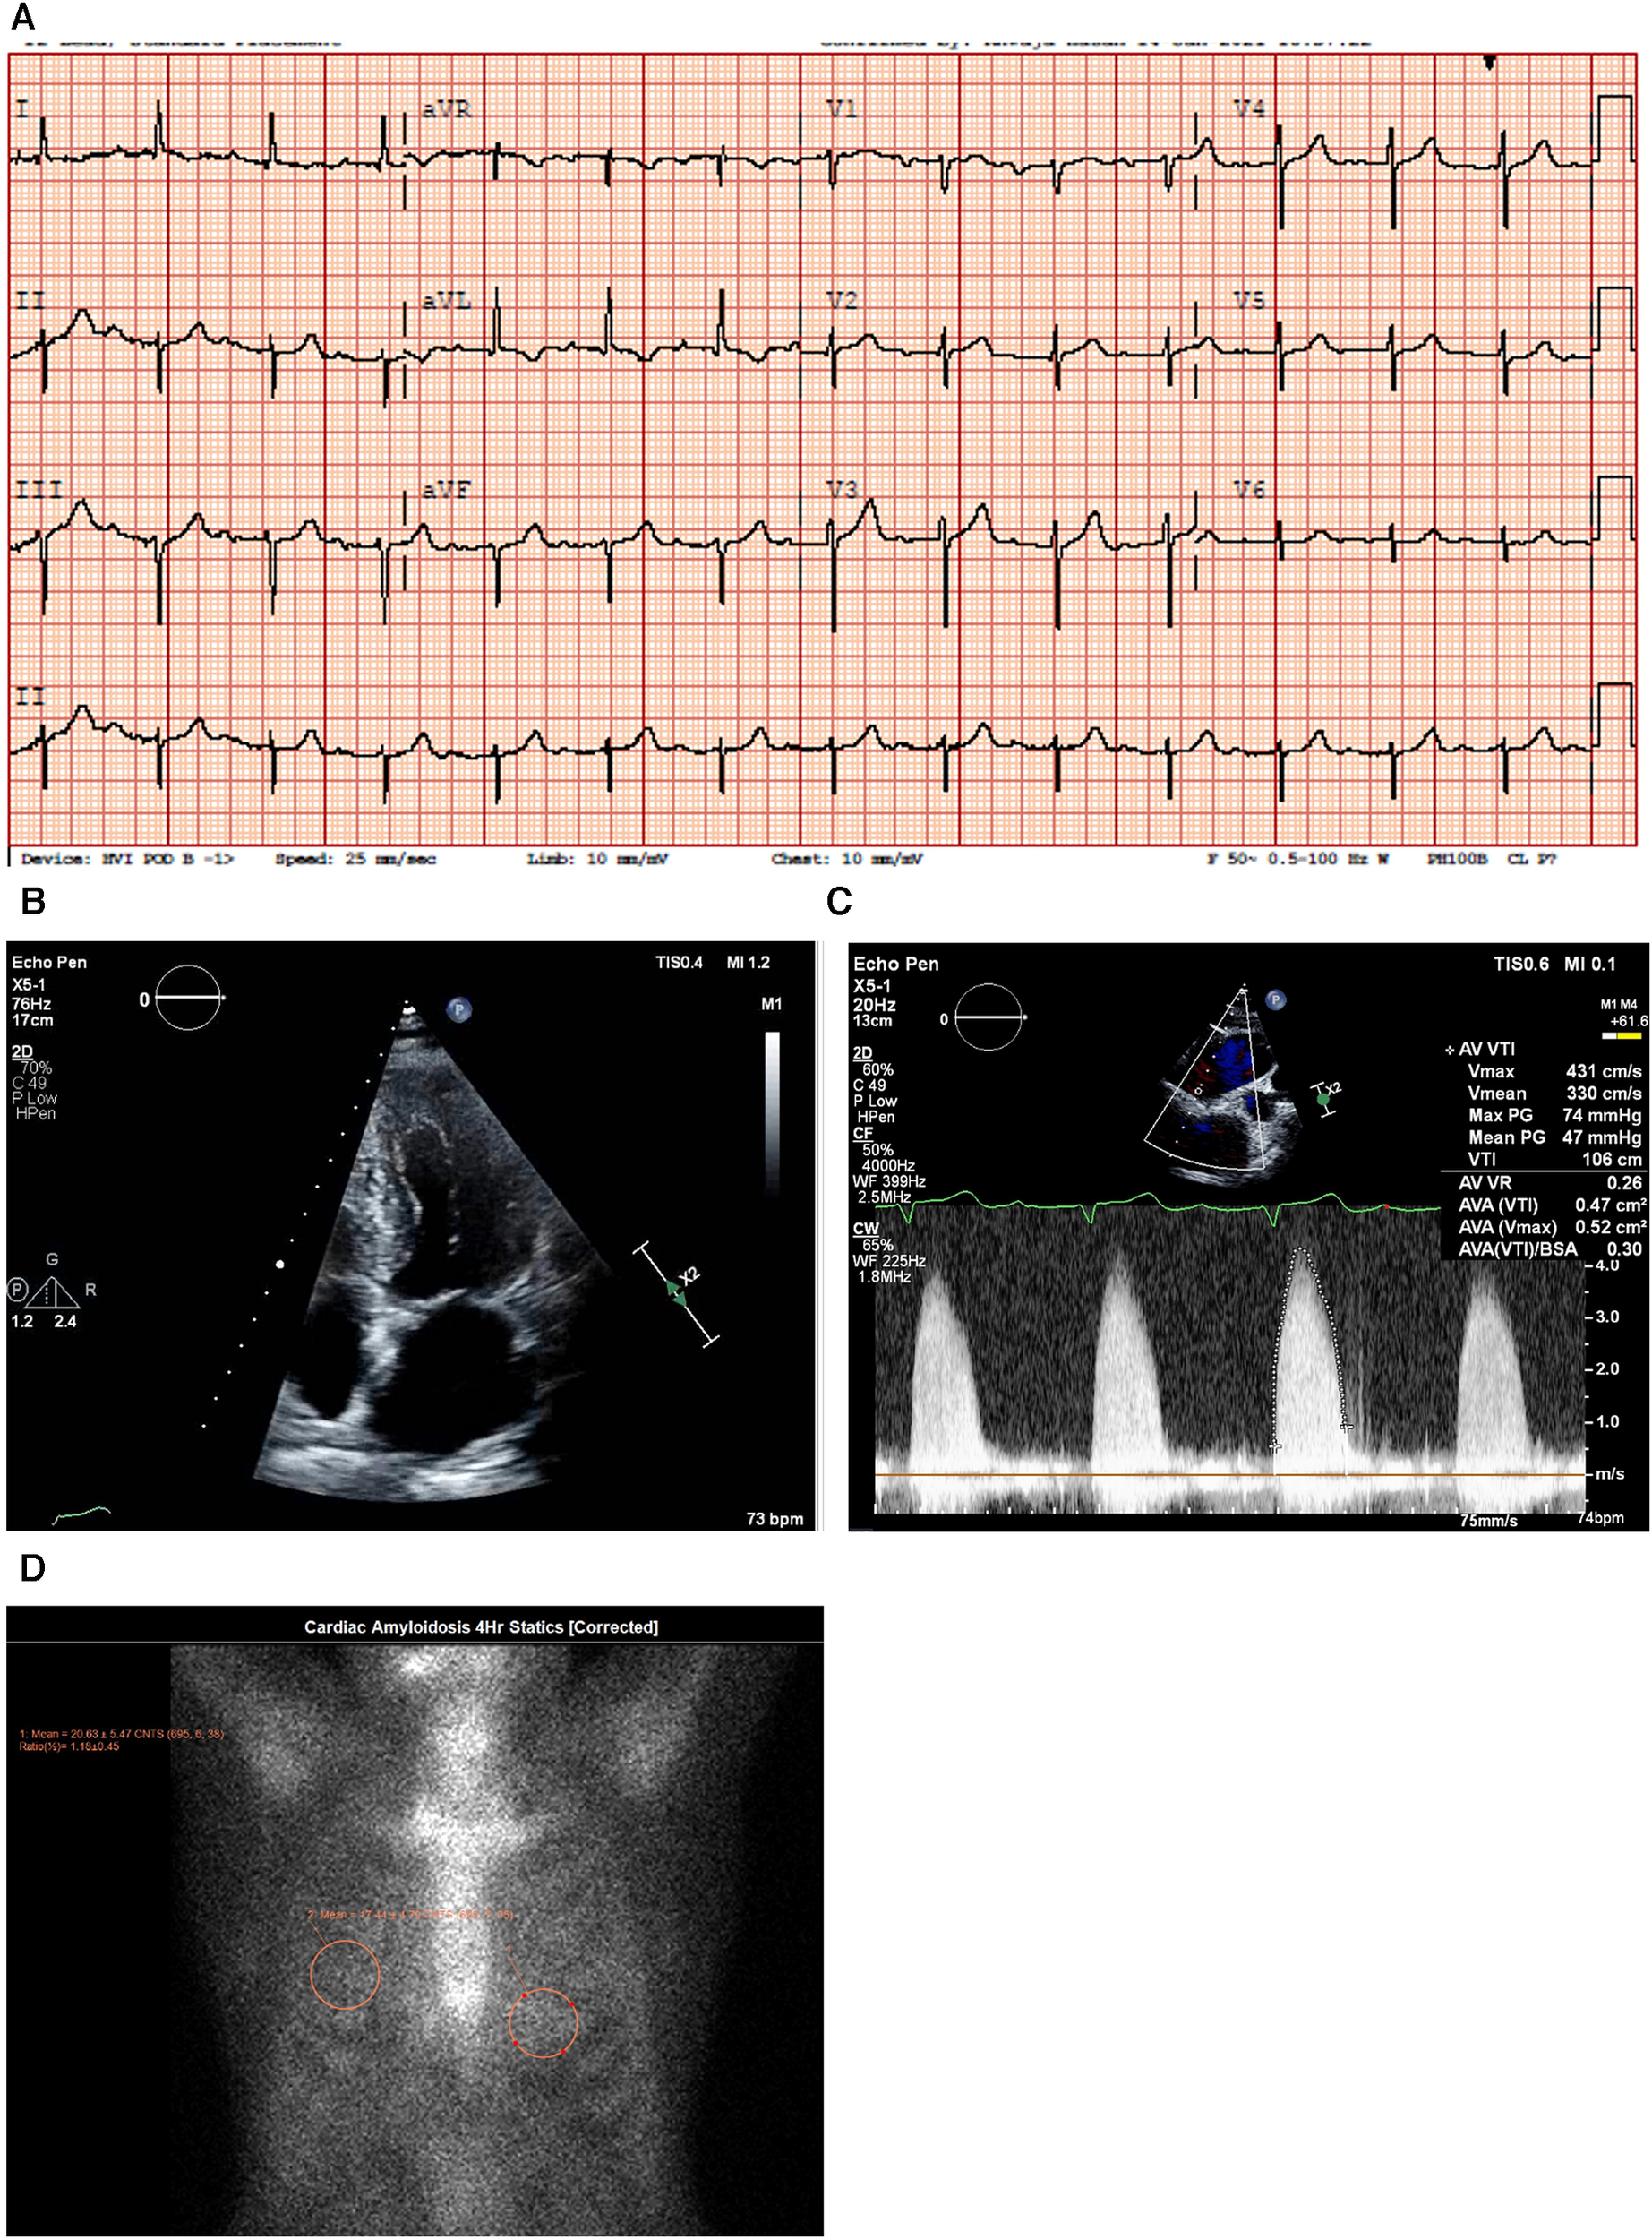

Figure 4

Case 4 clinical investigations. (A) An ECG showing normal sinus rhythm with prolonged PR interval, 360 ms first-degree AV block, T-wave inversion in aVL, and left-axis deviation with a left anterior vesicular block. (B) A 2D echocardiography with four-chamber view showing LV hypertrophy with a dilated left atrium and thickened atrial septum. (C) Continuous-wave Doppler of the AV consistent with AS. The calculated AV area was 0.5 cm2. (D) A planar bone scintigraphy (99mTc-PYP) scan at 4 h showing myocardial uptake that is less than rib uptake (grade 1).

AV, aortic valve; ECG, electrocardiogram; LV, left ventricular; 99mTc-PYP, technetium pyrophosphate.

An echocardiogram (Figure 4B) highlighted a normal-sized left ventricle with mild concentric LV hypertrophy (R). The LV systolic function was normal, and the EF was 64 ± 5%. The global LV myocardial strain was normal, and LV diastolic function was grade II. The left atrial cavity was mildly dilated, and the patient had mild to moderate mitral regurgitation. The right ventricle was normal in size and RV systolic function was normal. The E/A ratio was 1.0. Severe AV stenosis was demonstrated with a peak velocity of 4.3 m/s, a mean gradient of 47 mmHg, an AV area of 0.47 cm2, and an SVi of 32 ml/m2 (Figure 4C).

A hematological workup was performed, and the serum and urine immunofixation test results did not show monoclonal gammopathy. The serum kappa/lambda ratio was 2.06 and was determined to be negative for AL amyloidosis.

A PYP scan demonstrated that myocardial PYP uptake was less than rib uptake (grade 1), and SPECT-CT images did not demonstrate evidence of myocardial tracer uptake (Figure 4D).